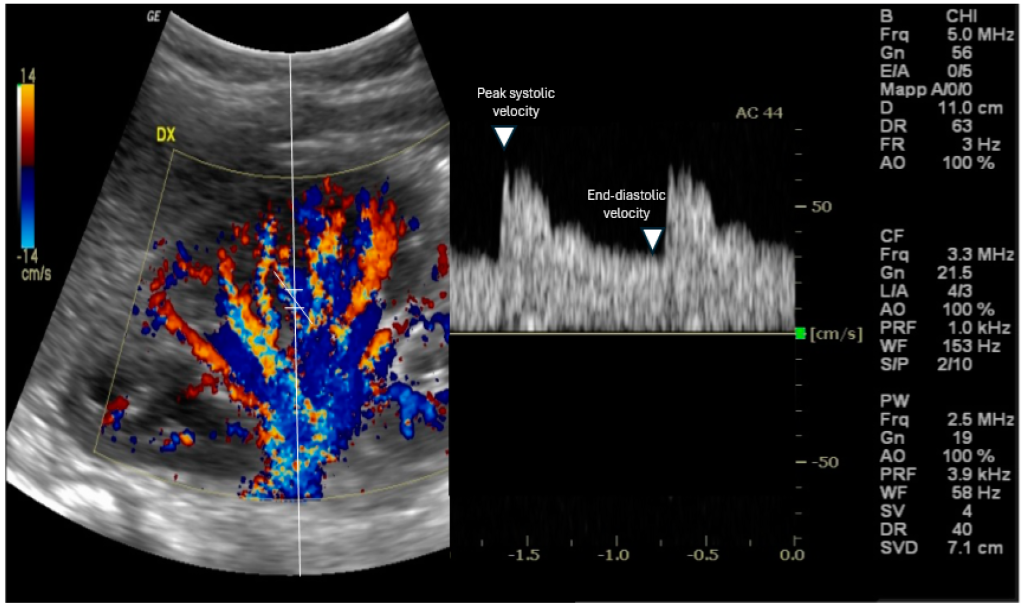

Summary of “Exploring the Utility of Renal Resistive Index in Critical Care: Insights into ARDS and Cardiac Failure” Abstract The renal resistive index (RRI), a Doppler ultrasound-derived metric, offers a non-invasive window into renal hemodynamics, especially relevant in patients with acute respiratory distress syndrome (ARDS) and heart failure (HF). This narrative review explores RRI’s physiological […]